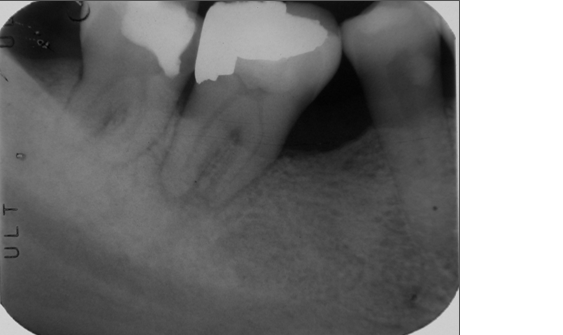

治療前,患者有二次蛀牙,產生不可逆牙髓炎

C型根管之下顎大臼齒

有關 C 型根管病例報告,最早由 Cooke 等學者在 1979 年提出3。C 型根管主要發生於下顎第二大臼齒,亦有少數病例報告發生於其他部位,如上顎第一4、第二大臼齒5、下顎第一大臼齒6,及合併的齒中齒上顎側門齒7。就下顎第二大臼齒而言,C型根管的發生率依人種及研究方式相異而有所不同,其中以亞洲人種為研究對象的結果顯示,C 型牙根(C-shaped roots)的發生率為 31.5%,而 C 型根管(true C-shaped canal)的發生率可達 13.9%。